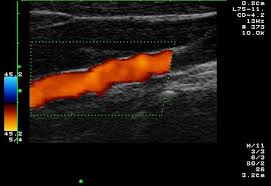

경동맥 초음파 검사는 고주파 초음파를 사용하여 목의 경동맥 혈관을 영상으로 확인하는 검사입니다. 혈관 내벽 두께, 혈류 흐름, 좁아진 정도 등을 실시간으로 볼 수 있으며, 조영제나 방사선 노출이 없어 안전합니다. 검사 시간은 약 20~30분 정도 소요됩니다.

환자는 검사 침대에 누운 후, 목에 젤을 바르고 초음파 탐촉자를 대어 경동맥을 관찰합니다.